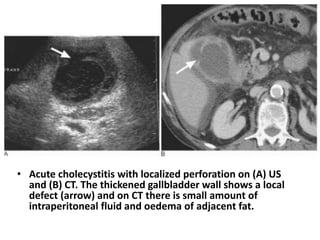

• Acute cholecystitis with localized perforation on (A) US

and (B) CT. The thickened gallbladder wall shows a local

defect (arrow) and on CT there is small amount of

intraperitoneal fluid and oedema of adjacent fat.

• Acute cholecystitiswith localized perforation on (A) US and (B) CT. The thickened gallbladder wall shows a local defect (arrow) and on CT there is small amount of intraperitoneal fluid and oedema of adjacent fat.